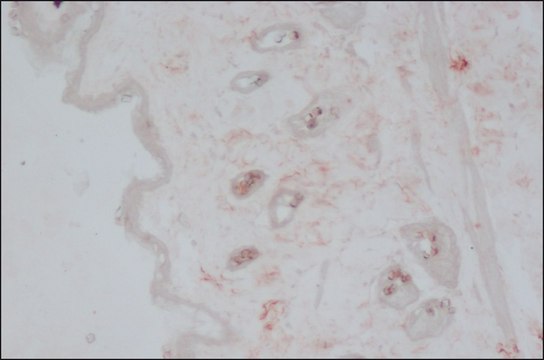

ELISA: suitable, immunoblotting: suitable, immunofluorescence: suitable, immunohistochemistry: 10-20 μg/mL using heat-retrieved formalin-fixed, paraffin-embedded rat skin sections.

Monoclonal anti-collagen type III specifically recognizes native and denatured collagen type III from human 1 and rat 2 origin. It does not recognize collagen types I, II, IV, V, VI and X.